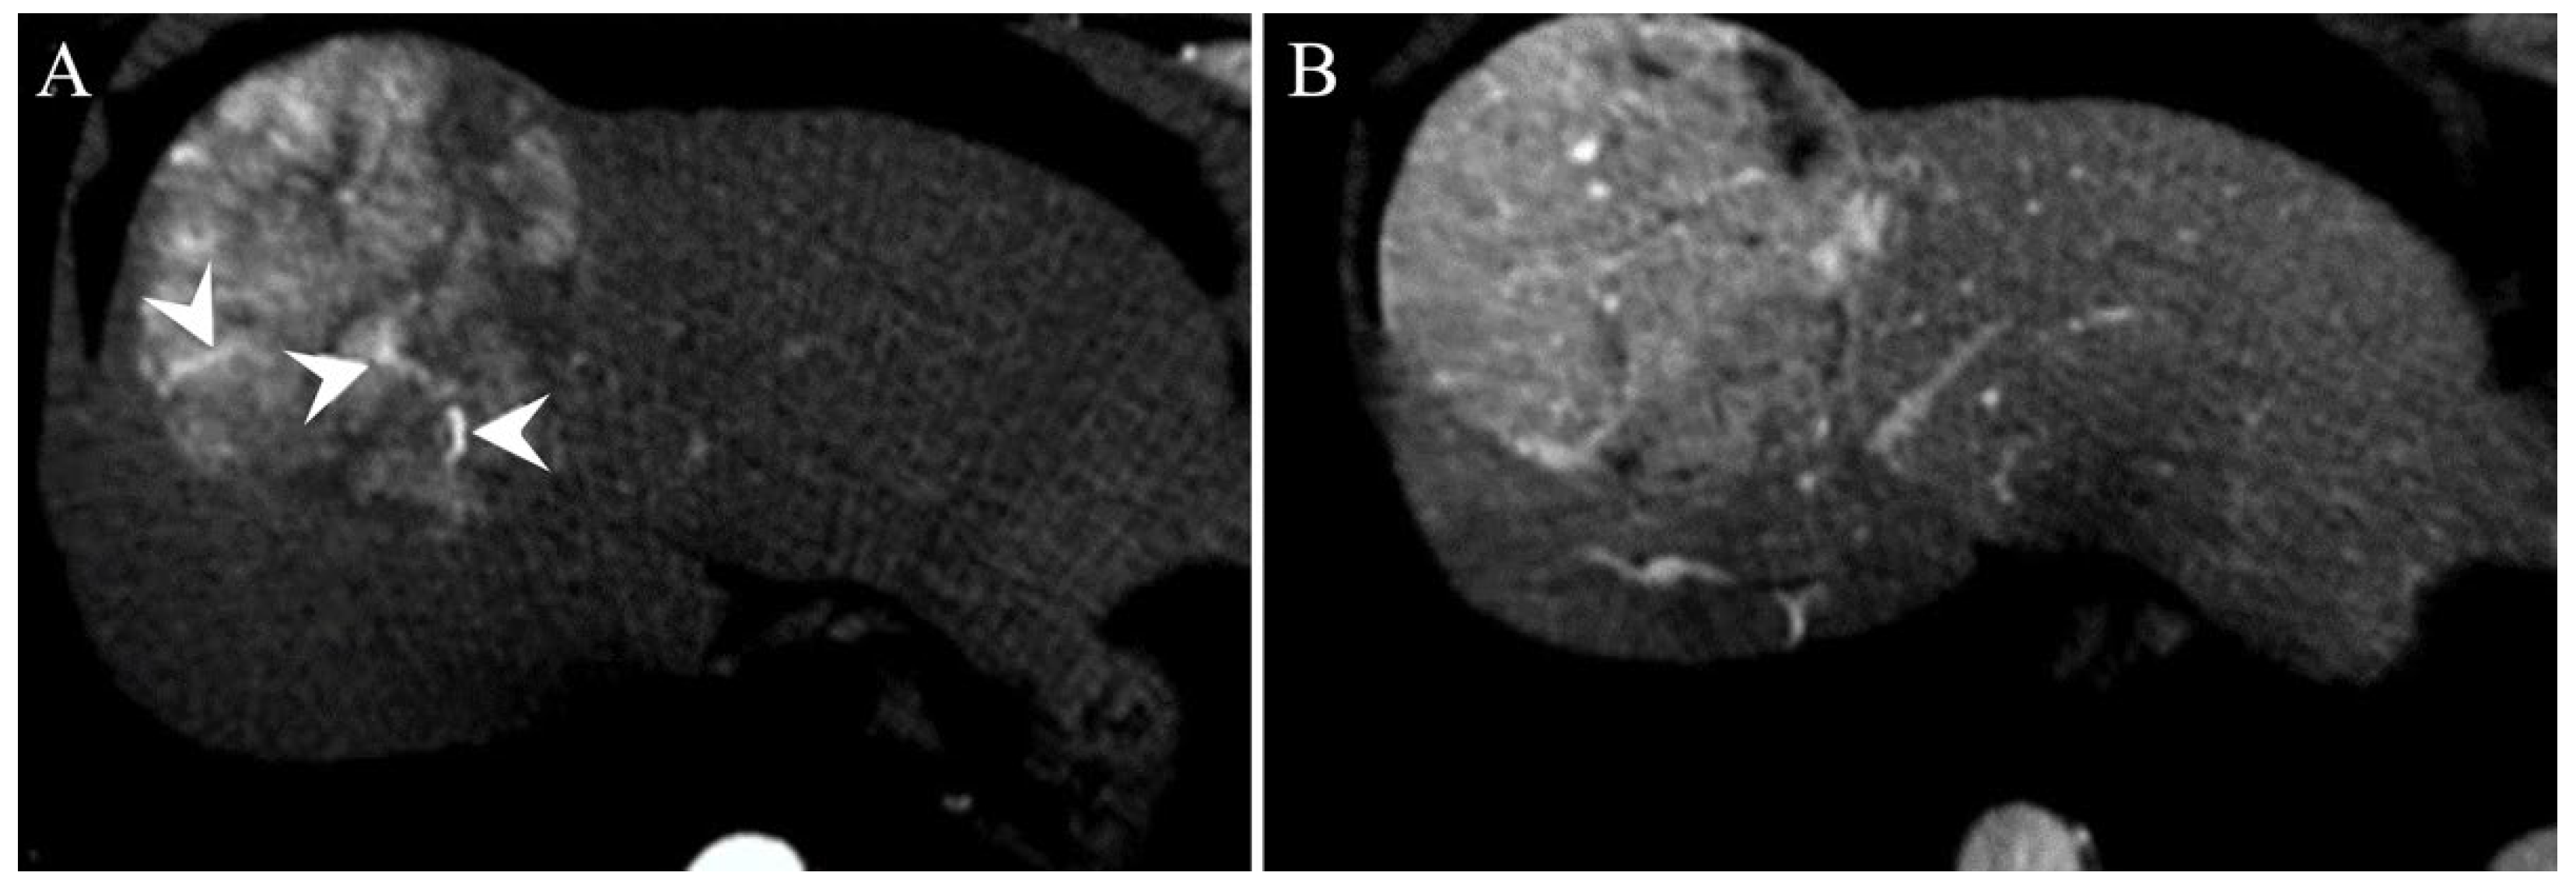

| Irregular margins | 21 (58.3%) | 26 (47.3%) | 0.391 |

| TTPVI | 14 (38.9%) | 11 (20%) | 0.058 |

| Peritumoral enhancement | 4 (11.1%) | 6 (10.9%) | 1.000 |